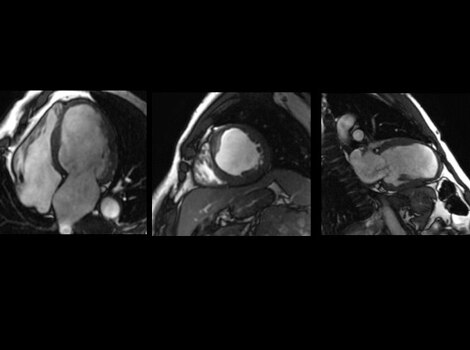

SIGNA™ Works CV Imaging & Analysis Tools

One non-invasive CMR exam to assess cardiac morphology, function, flow, tissue viability and coronary anatomy without ionizing radiation.

Cardiology Solutions Aortic Stenosis signaworks 1and 2

Cardiology Solutions Aortic Stenosis signaworks 3